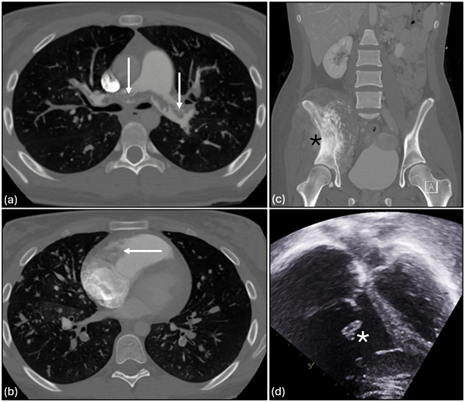

A 16-year-old girl presented with computed tomography findings of sub-massive bilateral pulmonary emboli and a tricuspid valve mass (Figure 1A and B); she was subsequently diagnosed with a 16-cm pelvic osteosarcoma (Figure 1C). Echocardiography confirmed a large thrombus on the tricuspid valve chordae (Figure 1D) and reduced right ventricular (RV) function with a preserved left ventricular ejection fraction (LVEF). Despite initiation of heparin, impending hemodynamic collapse prompted a multidisciplinary decision for percutaneous thrombectomy with VA-ECMO support.